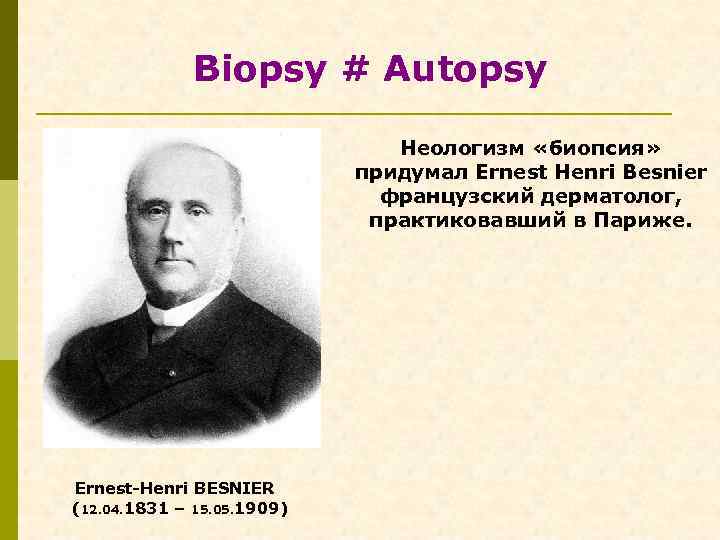

Biopsy # Autopsy Неологизм «биопсия» придумал Ernest Henri Besnier французский дерматолог, практиковавший в Париже. Ernest-Henri BESNIER (12. 04. 1831 – 15. 05. 1909)